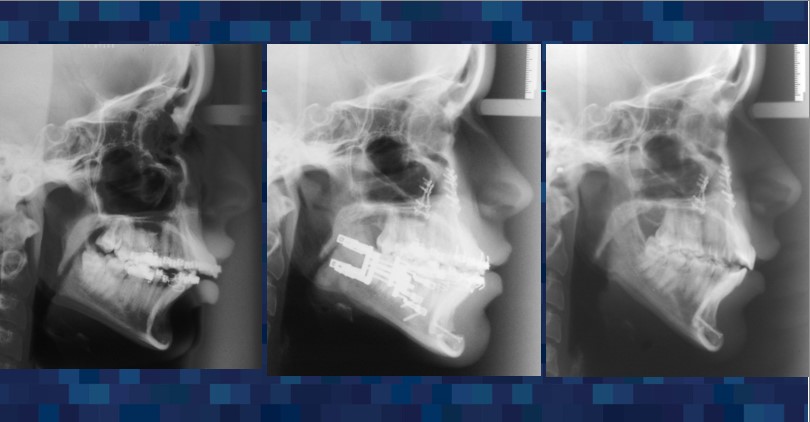

For over 30 years, Dr. Guerrero has made it his mission to improve the lives of his patients through specialized surgical care that restores function and comfort. Dr. Guerrero’s work embodies precision, compassion, and a dedication to patient well-being. Corrective jaw surgery is one of the advanced services offered, designed to address functional issues and enhance the quality of life for those who need realignment and reconstruction.